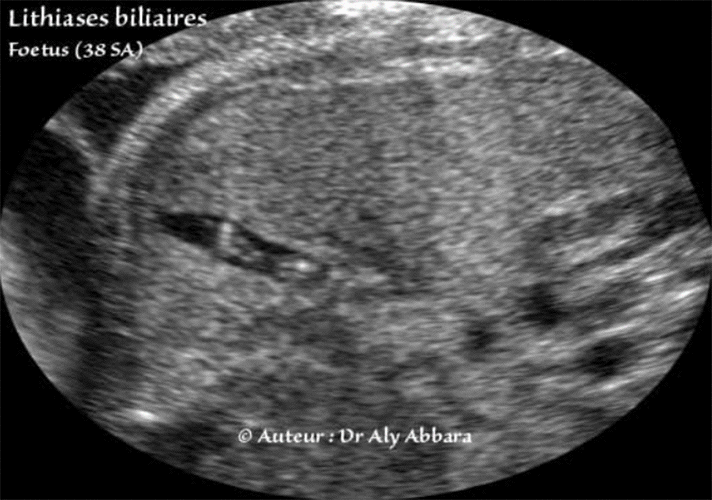

Lithiases biliaires - Foetus à 38 SA

Vésicule biliaire contenant des calculs (lithiases) biliaires

(Deux fœtus différents âgés de 38 SA).

• Coupes échographiques abdominales transversales centrées sur la partie inférieure du foie et montrant une vésicule biliaire contenant des images hyperéchogène traduisant la présence dans sa cavité de calculs biliaires.

On remarque l'absence d'atténuation distale acoustique (ou cône d'ombre) derrière ces calculs.

• Les calculs biliaires disparaissent habituellement dans les premières semaines de vie.